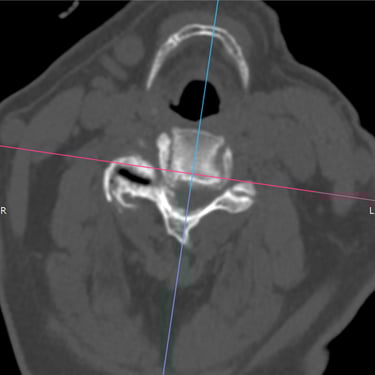

🧠 Cuerpo Extraño en la Región Posterior del Cuello | Cirugía Cervical.

La extracción de un cuerpo extraño en la región posterior del cuello requiere una cuidadosa cirugía cervical, guiada por estudios de imagen. Con técnicas microquirúrgicas se logra retirar el objeto de forma segura, preservando nervios y tejidos cervicales, y garantizando una recuperación adecuada sin comprometer la función neurológica.